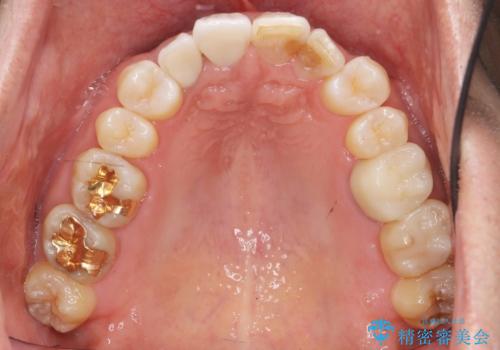

仕上がりに限界はありましたが、比較的短期間で歯並びが整いセラミック治療を行うことができ、患者様に「治療して良かった」とご満足頂けました。

左上1の歯の表面にもともと凹凸とグラデーションがあり、気になるようならセラミックでかぶせるのも一つだと提案しましたがご希望されなかったため、その表面性状を再現して右上1のセラミッククラウンを作製しています。

右上21:ジルコニアクラウン スペシャル

左上6:ジルコニアクラウン スタンダード

左上7:e-max press セラミックインレー